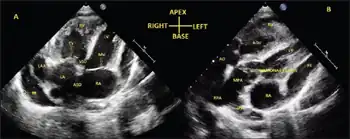

| a) Transthoracic echo in apical 4-chamber view shows inverted atria b) D-transposition of great arteries | |